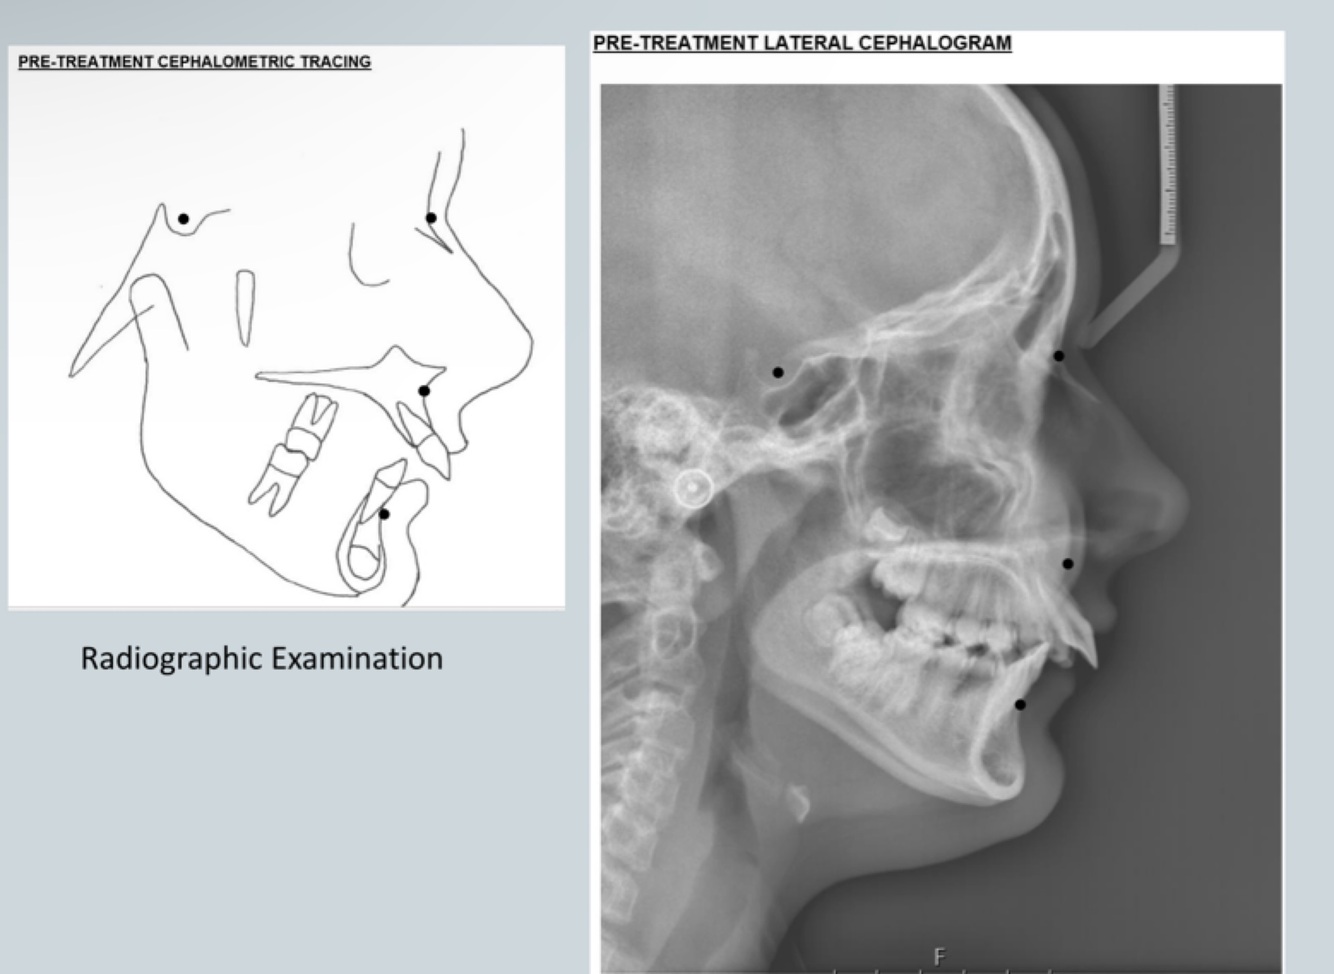

Identify

Cephalometric measurements can identify position of upper jaw in relation to cranial base and lower jaw in relationship to cranial base and so relationship of maxilla to mandible

As pt skeletal class II - we can see patients lip trained behind upper incisors and so proclining upper incisors - so this pt has multi factorial aetiology:

- position of maxilla to mandible

- soft tissue trap